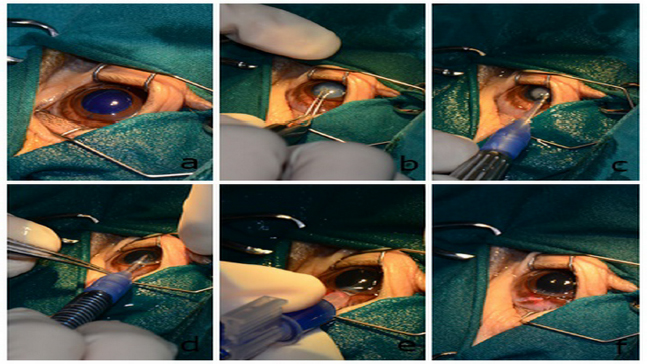

Pre-surgical preparation and phacoemulsification technique

Fig. 6. Selected steps of the one-handed technique of phacoemulsification and IOL implantation OD. Anterior lens capsule was stained with trypan blue (a). Utrata capsulorhexis forceps were used to accomplish continuous curvilinear capsulorhexis with 6–8 mm diameter (b). One-handed phacoemulsification and aspiration technique were carried out (c). Irrigation and aspiration were then applied to remove all lens fibers (d). A +23.5 diopter IOL was inserted through the limbus incision to restore proper vision (e). The surgical wound at 11 o’clock was sutured with polyglycolic acid 9/0 (f).